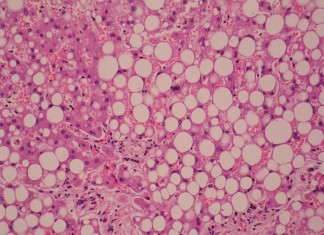

Los científicos consiguen reprogramar células de grasa para quemar calorías

Los científicos han descubierto el mecanismo genético a través de la cual las células de grasa blanca pueden ser reprogramadas para ser como las...